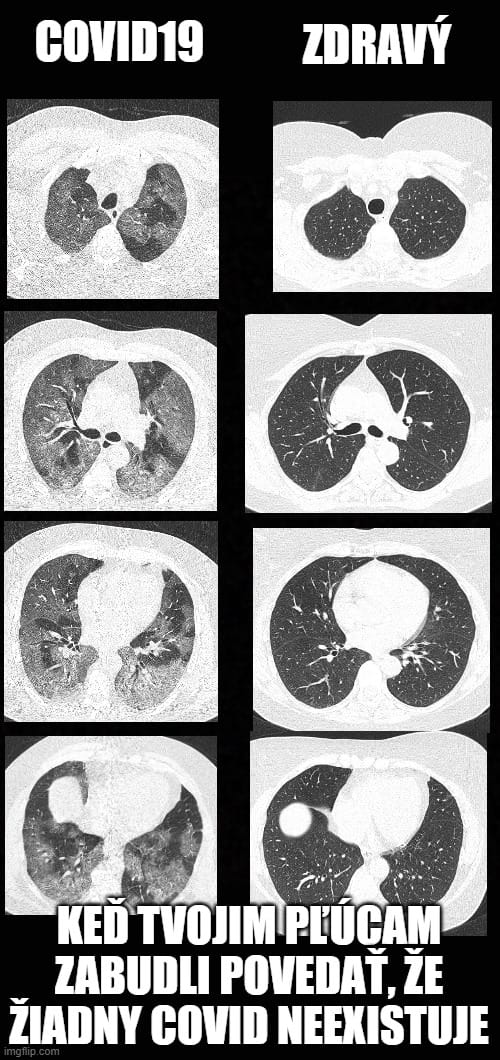

Totálny hoax. Tieto fotky nemuseli ani vzniknúť cez koronu. Pri každom vážnom respiračnom ochorení sa ti na pľúcach vytvorí takýto obraz. Pľúca máš v piči (čisto logicky) aj pri zápale pľúc, ktorý síce môže byť spôsobený aj Covidom, ale mali sme ho tu už aj pred covidom, či ne?

http://www.mevis-research.de/~hhj/Lunge/SammlungInf2.html V tomto linku si nájdi vľavo na kraji: ausgedehnte Bronchopneumonie beidseits, basal konfluierend. Verlauf a potom si preklikaj: bei Aufnahme, nach drei Tagen, nach neun Tagen. Ale za zhliadnutie stoja aj ostatné obrázky.

zadny hoax, ale bohuzel fakt, ale chapu ze se ti to nelibi... zdroj mam overen... kolega zna primo autora techto memes, a pracuje jako radiolog v nemocnici...

Práve som chcel dať edit k môjmu príspevku, ale už to nešlo, keďže si odpovedal.

Nemyslel som hoax v tom zmysle, že toto covid nemôže spôsobiť. Za hoax považujem tú účelovosť, s jakou sú tieto obrázky šírené, akoby toto spôsoboval iba covid a doteraz sme sa tu s ničím takým nestretli.

Tú reportáž tiež nespochybňujem, len by sa to hodilo porovnať aj s ostatnými ochoreniami. Takého niečoho sa ale nedočkáme...